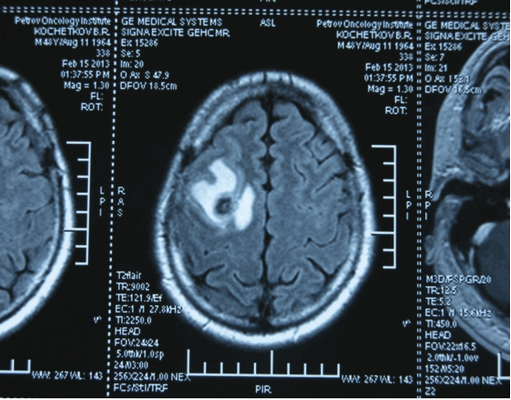

Головной мозг

Герминогенные новообразования в данной области - это примерно 2-4% от всех внутричерепных (интракраниальных). Патология в 75% случаев диагностируется у мальчиков, за исключением турецкого седла, где новообразования в основном локализуются у девочек.

Герминомы формируют инфильтрирующие опухоли больших размеров, часто являющиеся источниками субарахноидальных (между мягкой и паутинной оболочками мозга) и вентрикулярных (желудочковых) метастаз.

Рисунок 7. - Герминома головного мозга.

- КТ (расшифровка: компьютерная томография), МРТ (расшифровка: магнитно-резонансная томография), ПЭТ-КТ (расшифровка: позитронно-эмиссионная томография, совмещенная с КТ). Эти обследования необходимы, чтобы рассмотреть структуры организма послойно и визуализировать опухоль. Они показывают, как сильно распространен патологический опухолевый процесс на находящиеся рядом ткани и органы, есть ли поражение костей. КТ - это самый чувствительный метод для обнаружения метастазов в легких. Проведение МРТ и КТ головного мозга необходимо, чтобы обнаружить и визуализировать герминогенные новообразования эпифиза.

Рисунок 9. - метастаз в головной мозг при герминогенной опухоли.

Лучевая терапия показана чаще при локализации процесса в головном мозге. Она позволяет точно, локально воздействовать на опухоли.

Герминогенные опухоли центральной нервной системы (головного мозга) имеют следующие клинические проявления: головная боль, расстройство движений глазных яблок, тошнота, рвота и развитие судорог.

Также выполняют МРТ головного мозга, чтобы выявить наличие метастазов в нем.

![Метастаз в головной мозг при герминогенных опухолях (МРТ головного мозга)]()

Метастаз в головной мозг при герминогенных опухолях (МРТ головного мозга)

Лучевая терапия назначается чаще при поражении головного мозга. Ее применение обусловлено возможностью точного локального воздействия на опухолевые массы.

Лучевая терапия при опухолях яичка в настоящий момент практически не используется, так как имеет низкую эффективность. Применение лучевой терапии может использоваться в качестве локального (местного) контроля при метастазах в головном мозге.